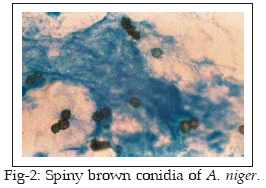

Fifteen patients attending at the Jahad and Razi Laboratories supposed to be suffering from disease were involved in this investigation. It included 11 female (73.3%) and 4 males (26.7%). The ages of the patients ranged between 4-30 years with a mean of 17 years. All patients had one or more of the aural symptoms (itching, otalgia, hearing loss). Secretion and pus were collected from the ear by two sterile cotton wool swabs. One swab was used for direct microscopy and other for culture examination. Direct examination of the samples was carried out by staining the smears with methylene blue and Gram techniques. Otomycosis was confirmed by the presence of aseptate mycelium, septate mycelium, Aspergillus conidia, fruiting bodies, yeast and pseudohyphae (Figs 1-4). The presence of fungal elements in stained smears was re-confirmed by fungal culture fungal colonies. Any kind of clinical materials, especially liquid samples (swabs, pus) should be examined as quickly as possible. Swabs did not require processing and were directly used for culture. Swabs were rolled and inoculated over the surface of Sabouraud’s Dextrose Agar with chloramphenicol (SC). Cultures were incubated at laboratory ambient (25-27°C) for 2-3 weeks, aerobically. Fungal isolates (moulds) were identified on the basis of colonial morphology and slide cultures. Yeast colonies, also detected by germ tube test, production of chlamydoconidia on corn meal agar and API 20 C AUX system.

Results